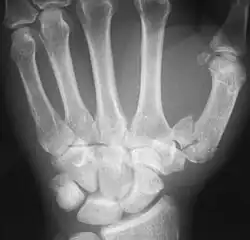

Bei der Bennett-Fraktur (auch Bennett-Luxationsfraktur) handelt es sich um eine Fraktur an der Basis des ersten Mittelhandknochens, die bis in das Daumensattelgelenk zieht. Der Mittelhandknochen wird durch den Zug der hier ansetzenden Sehne des M. abductor pollicis longus nach proximal verschoben. Meist bleibt ein kleineres dreieckiges Fragment ulnar am Gelenk stehen.

Die Fraktur entsteht meist bei einem Stauchungstrauma auf den adduzierten Daumen.

Die Reposition wird mit Abduktion des Daumens durchgeführt. Je nach Repositionsergebnis erfolgt dann eine konservative Ruhigstellung (Gipsverband) oder eine operative Stabilisierung.